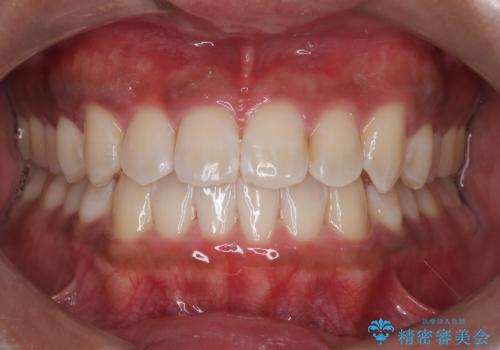

- 矯正中に歯の表面の掃除、歯を白くしたいとのことで来院されました。

PMTCとオフィスホワイトニングを行いました。

ステインが全体的についていたのでPMTCでステインを除去しオフィスホワイトニングを行いました。

ホワイトニングは薬剤を塗布し、レーザー照射を三回行いました。